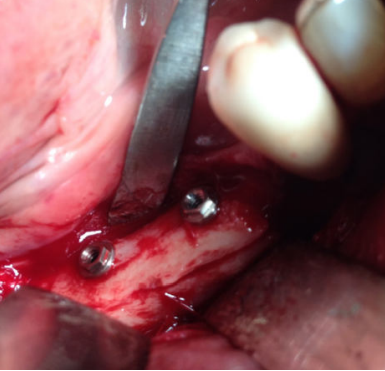

El injerto en bloque obtenido se dividió con la ayuda de un disco de corte en dos láminas corticales de 1,5 mm (Figura 4). Seguidamente, se fijó una de las láminas en la parte coronal del defecto óseo, creando un espacio virtual en altura de aproximadamente 6 mm que se rellenó con las partículas de hueso autógeno obtenidas (Figura 5). La lámina remanente se posicionó y fijó conformando la pared vestibular del defecto (Figura 6). La sutura se llevó a cabo mediante puntos de colchonero, favoreciendo así la cicatrización, y se utilizó monofilamento de 5/0. El CBCT postquirúrgico de control mostró una correcta reconstrucción tridimensional del defecto y el postoperatorio cursó con normalidad, sin signos infecciosos ni dehiscencias de la herida y sin alteraciones sensitivas (Figura 7).